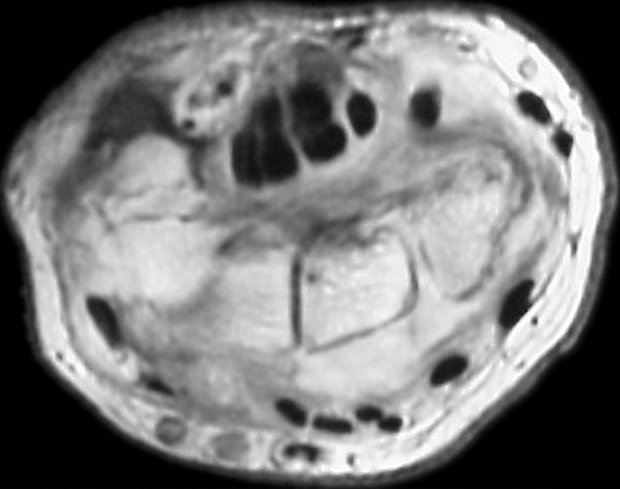

MRI revealed poorly defined soft tissue prominence deep to the extensor tendons and small cystic carpal changes.